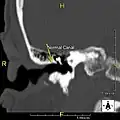

-

Normal ear canal -

Exostosis in ear canal -

Exostosis in ear canal